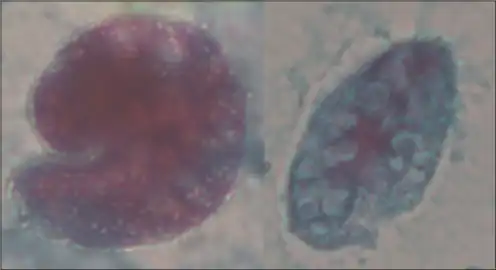

Balantidium coli has two developmental stages, a trophozoite stage and a cyst stage. In trophozoites, the two nuclei are visible. The macronucleus is long and sausage-shaped, and the spherical micronucleus is nested next to it, often hidden by the macronucleus. The opening, known as the peristome, at the pointed anterior end leads to the cytostome, or the mouth. Cysts are smaller than trophozoites and are round and have a tough, heavy cyst wall made of one or two layers. Usually only the macronucleus and sometimes cilia and contractile vacuoles are visible in the cyst, however, both nuclei are present because nuclear multiplication does not occur when the organism is a cyst.[3] Living trophozoites and cysts are yellowish or greenish in color.[4]

Trichrome stained trophozoites of Balantidium coli